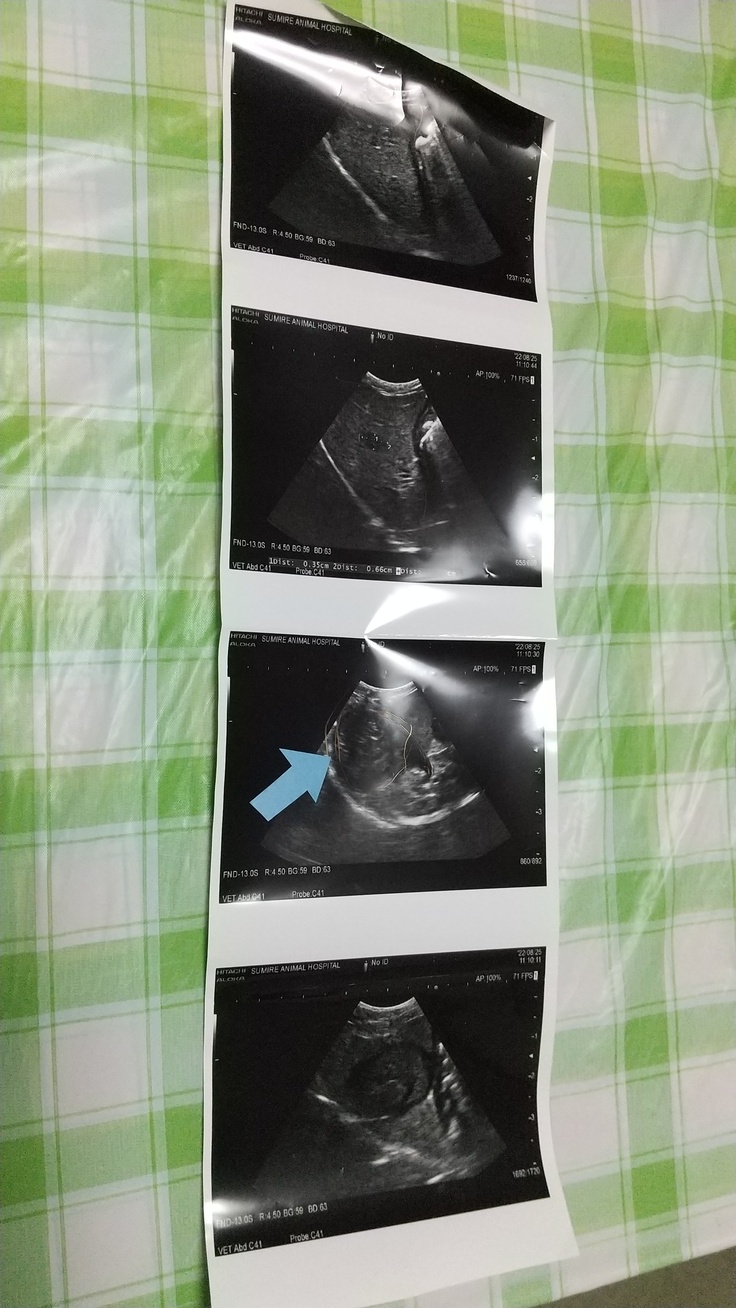

▩どんな症状や病気、疾病の治療▩

肝疾患の値がかなり高く、淡白も

炎症を起こしている、尿比重も高い。8/25の画像です。

▩その為エコーを撮りました。▩

▩病名は「たんのうめんえきのうしゅ」▩

総胆管が詰まって胆汁が血液の中に逆流して全身を巡り黄疸吐き気が起こったものと思われる。手術が必要なのは胆嚢炎から胆嚢壁が虚血壊死して胆嚢破裂を起こす危険性がある。エコー画像有り。

エコーだけでは疑わしとしか判断出来ないがCT検査には17才という年齢にリスクをともなう為おすすめ出来ない。

4日後に診察に行きました。少しは落ち着いたものの肝疾患と尿淡白の値が高いです、画像有り。8/29の画像。